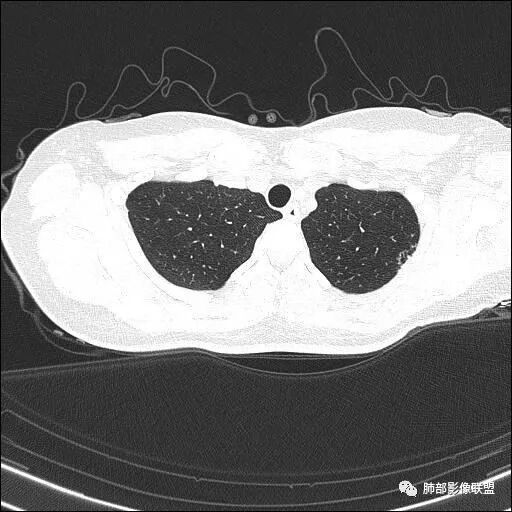

【每日晨读】双肺上叶多发薄壁空洞

1.年轻女性,体检发现肺部病灶

血常规正常

2.双肺多发薄壁空洞影、条索影及结节影,边界较清楚,密度偏高不柔和,散乱,但有成簇倾向或堆积感,胸膜下分布为主,双肺上叶分布为主。

3.空洞相当不规则,缺乏张力,未见血管穿行,未见壁结节,未见液平。

4.双肺门及纵隔未见肿大淋巴结。未见胸腔积液。